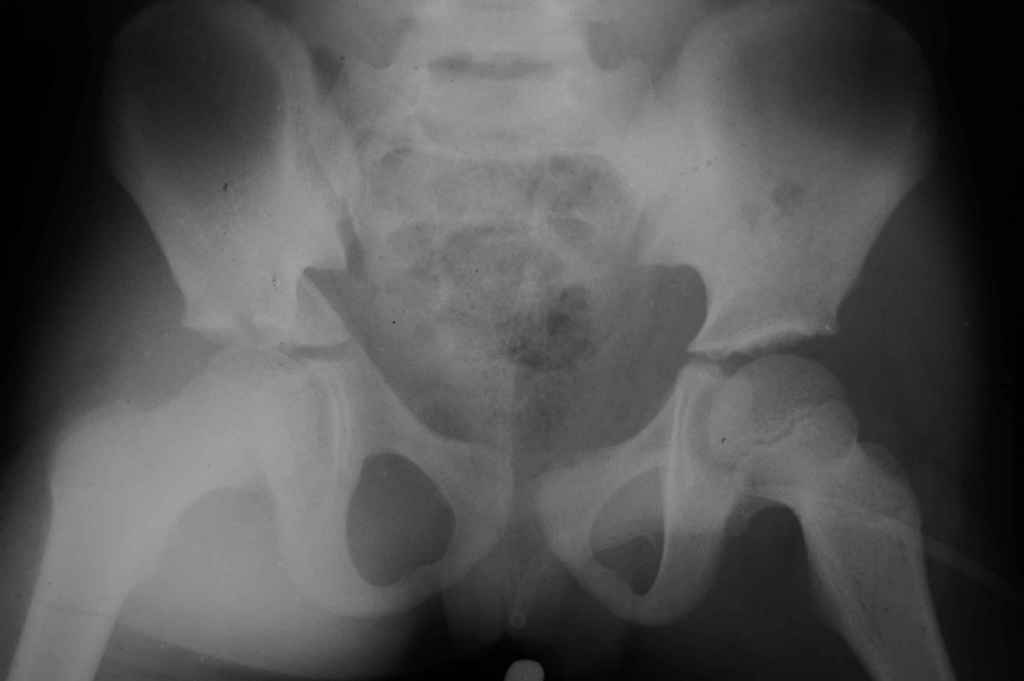

Перелом вертлужной впадины

Уважаемые коллеги, помогите определиться с тактикой лечения.Ребёнок 7 лет, травма 11.09.08, поступил с травматическим вывихом бедренной кости.

Вывих вправлен, конечность фиксирована на скелетном вытяжении. Что делать с переломом подвздошной кости? Лечить консерватино или оперировать?